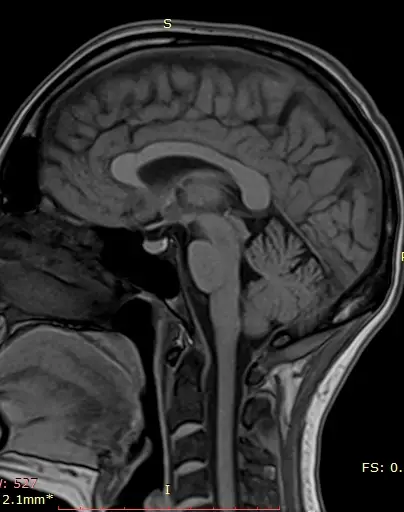

МРТ артерий головного мозга (ангиография)

Диагностика состояния артериальных сосудов головного мозга, выявление аневризм, стенозов и других сосудистых аномалий.